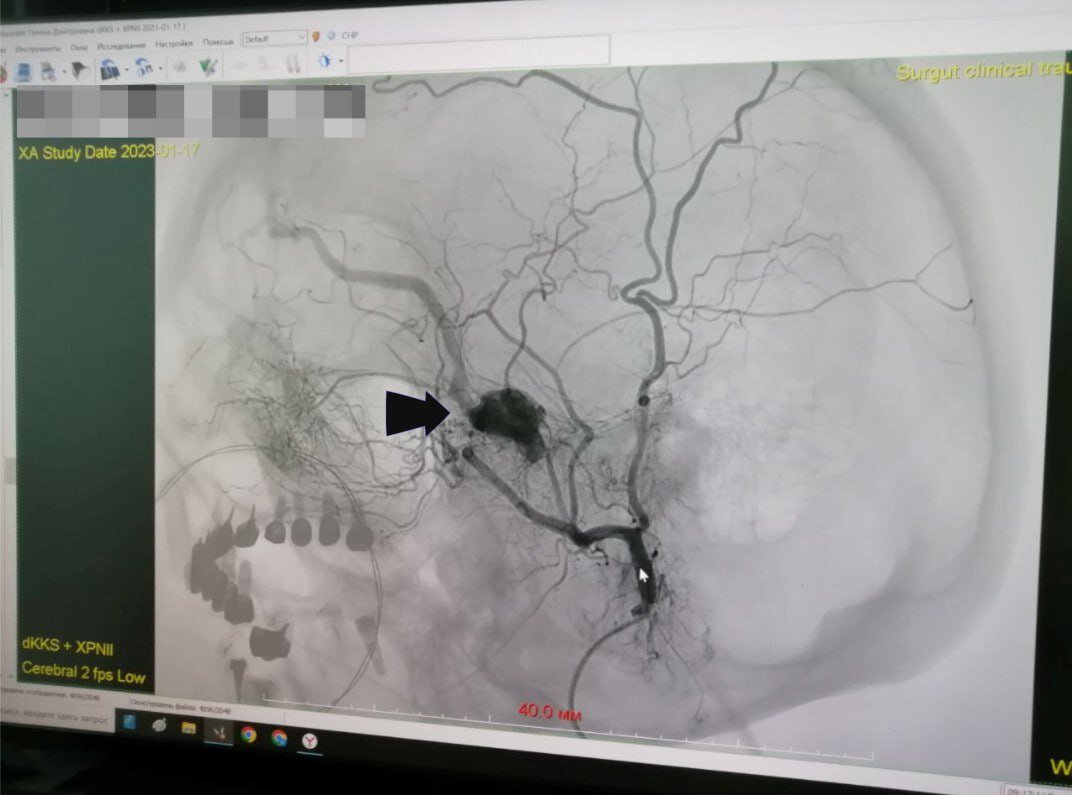

Хирурги Сургутской клинической травматологической больницы провели 12-часовую операцию, чтобы спасти 65-летнюю пациентку от слепоты. Процедура на головном мозге была настолько сложной, что ее пришлось разделить на два дня и привлечь нейрохирургов. Горожанка обратилась к врачам с жалобой на то, что у нее внезапно стало двоиться в глазах. Многочисленные обследования показали серьезность проблемы. У пациентки выявлена артериовенозная фистула – сосудистая аномалия, она возникает после травм, при тромбозах и по ряду других причин. – В данном случае образовалось соустье артерии, питающей лицо, и вены, дренирующей головной мозг. Давление в артериях выше, поэтому, когда кровь отсюда попадает в вены, они раздуваются и начинают притеснять окружающие структуры. В частности, у нашей пациентки, от этого страдал зрительный нерв. Отсюда и проблемы, которые в дальнейшем только усугублялись бы. То есть глаз мог полностью утратить свои функции. Но в первую очередь эта аномалия опасна тем, что может спро

Горожанка обратилась к врачам с жалобой на то, что у нее внезапно стало двоиться в глазах. Многочисленные обследования показали серьезность проблемы. У пациентки выявлена артериовенозная фистула – сосудистая аномалия, она возникает после травм, при тромбозах и по ряду других причин.

– В данном случае образовалось соустье артерии, питающей лицо, и вены, дренирующей головной мозг. Давление в артериях выше, поэтому, когда кровь отсюда попадает в вены, они раздуваются и начинают притеснять окружающие структуры. В частности, у нашей пациентки, от этого страдал зрительный нерв. Отсюда и проблемы, которые в дальнейшем только усугублялись бы. То есть глаз мог полностью утратить свои функции. Но в первую очередь эта аномалия опасна тем, что может спровоцировать внутримозговое кровоизлияние. Кроме того, мозг при ней недополучает из крови кислород и другие питательные вещества, – рассказал заведующий отделением рентгенохирургических методов диагностики и лечения Сургутской травмбольницы Максим Бессмертных.

Главной сложность во время операции было подобраться к фистуле по сосудам. Ситуация усложнялась наличием у пациентки серьёзного заболевания почек.

– Лечение заключается в эмболизации фистулы. Её закрывают, плотно утрамбовывая специальной спиралью. Качественного изображения на мониторе добиваются контрастными препаратами. Но на сей раз из-за объёмы вводимого контрастного вещества пришлось существенно сократить. При этом фистула оказалась одной из самых труднодоступных в клинической практике наших врачей. Операцию они проводили в течение двух дней подряд – и в общей сложности затратили на неё 12 часов, – рассказали в пресс-службе медицинского учреждения.